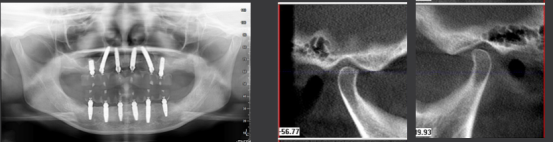

· 术后CBCT检查可见种植体植入位置佳,与术前设计一致。

· 修复体戴入后髁突位于关节窝内的适中位置。

· 植入精度分析,误差较小。

· X线片显示,种植体周骨稳定性、关节髁突位置评估均无异常。